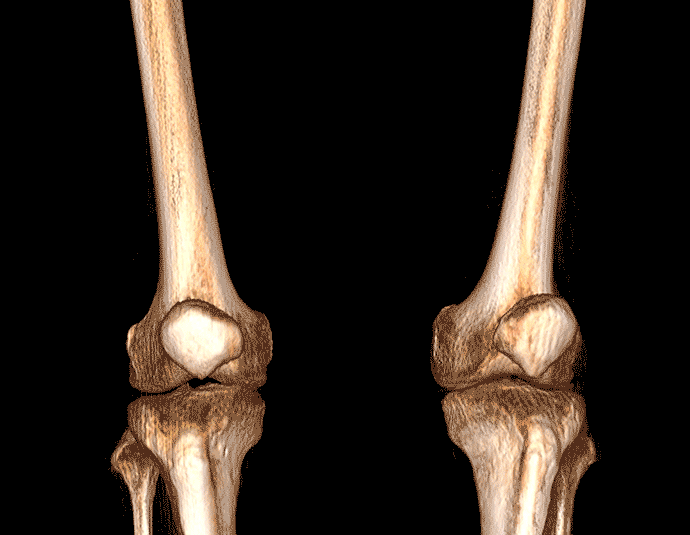

膝關節

精準診斷

手術方案規劃

術后隨訪